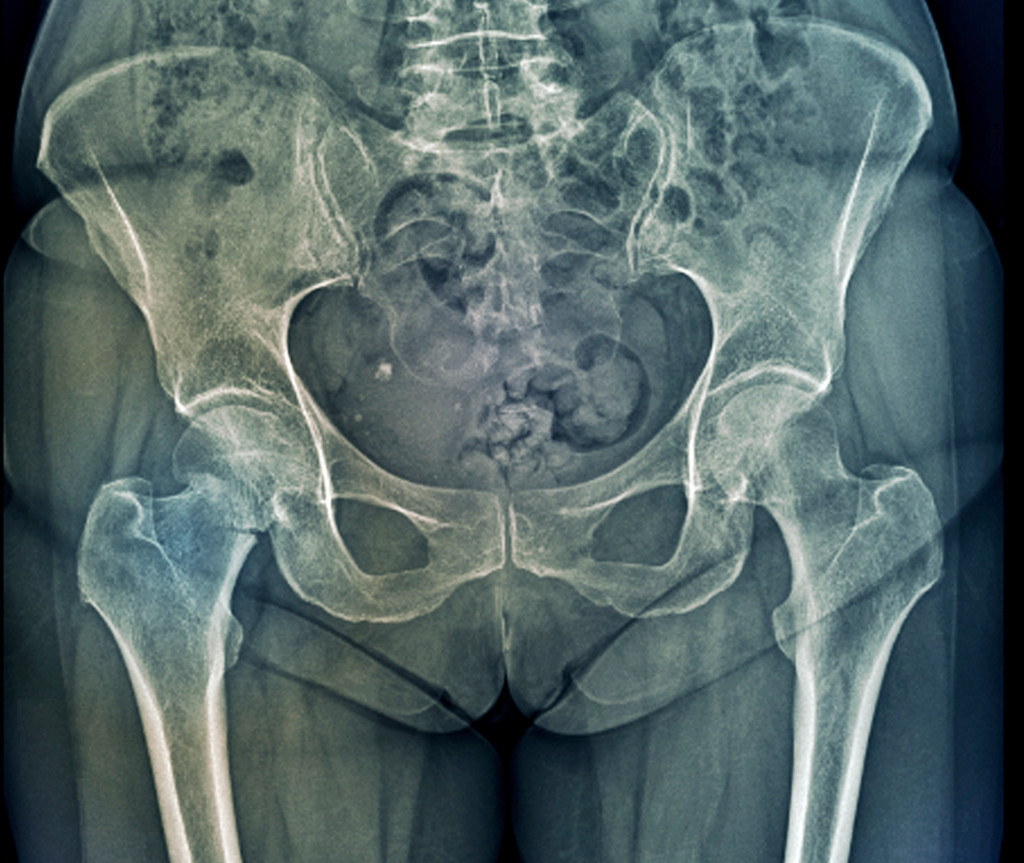

Høyresidig hoftebrudd. Illustrasjonsfoto: Science Photo Library / NTB scanpix